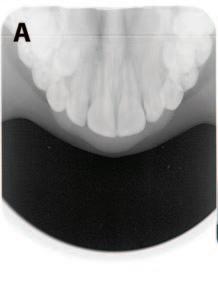

Visual examination for caries detection

Visual examination for caries using the merged-ICDAS system can be an important aid to minimally invasive dentistry.